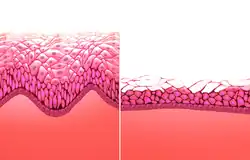

Mikroskopische Anatomie der Vagina, Wandaufbau

Die Vaginalwand ist mit einer Wandstärke von etwa drei Millimetern sehr dünn.[5] Die Vaginalschleimhaut (Tunica mucosa vaginae) trägt ein mehrschichtiges, unverhorntes Plattenepithel (Vaginalepithel), das nur eine minimale Präkeratinbildung zeigt. Sie ist glykogenreich und drüsenlos (kutane Schleimhaut). Das Epithel liegt auf einer Lamina propria, die reich an elastischen Fasern und weitlumigen Venen ist.[8] Das Epithel unterliegt im Verlauf des Sexualzyklus ständigen Umbauprozessen (→ Vaginalzytologie), die durch Estrogene und Progesteron gesteuert werden.[7]

Im Querschnitt zeigt die Vagina von innen nach außen folgenden Wandaufbau: Schleimhaut, Muskelschicht und Bindegewebsschicht.

Schleimhaut

Die Schleimhaut (Tunica mucosa vaginae) bestimmt die Oberflächenbeschaffenheit und sorgt für ein saures Milieu (pH-Wert 4 bis 4,5) durch die abgestorbenen Zellen des Vaginalepithels, die aufgrund des sehr hohen Glykogenanteils ein gutes Substrat für Milchsäurebakterien (Döderlein-Bakterien) darstellen und zur Ausbildung der speziellen Vaginalflora führen, was der Ansiedlung von Bakterien entgegenwirkt. Zur Tunica mucosa vaginae werden das eigentliche Vaginalepithel und die darunter liegende Lamina propria gezählt. Das Epithel der Vagina ist ein mehrschichtiges, unverhorntes Plattenepithel, das sich weiter in vier Schichten differenziert:

- Basalzellschicht (Stratum basale)

- Parabasalschicht (Stratum parabasale)

- Intermediärschicht (Stratum intermedium)

- Superfizialschicht (Stratum superficiale)

Diese Schichten sitzen der Lamina propria auf, die aus lockerem Bindegewebe besteht, das reich an elastischen Fasern und Lymphozyten ist. In der Lamina propria finden sich Kapillaren und Lymphgefäße, aus denen bei sexueller Erregung ein Transsudat durch das Epithel in die Vagina abgepresst wird, sowie der Plexus venosus vaginalis. Die nervale Innervation der Vagina beziehungsweise ihre Sensibilität ist nur gering. So finden sich nur wenige freie Nervenendigungen, sensorische Fasern fehlen gänzlich.